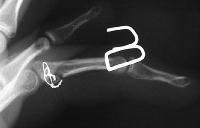

Intraoperative fixation and motion: Initial attempts of micro screw fixation were not successful, and wire cerclage was used:

Because of questionable stability of the fixation, a Dynamic Traction Splint for Proximal Interphalangeal Joint Fracture Dislocations was used: